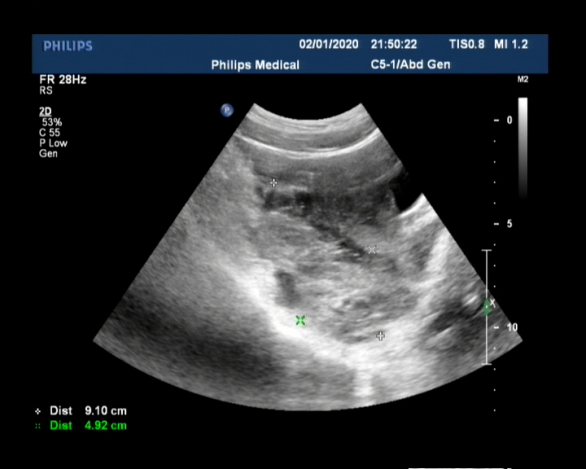

【超声表现】 经阴道超声探查子宫大小形态正常,内回声均匀,内膜厚约9mm,居中,宫内未见明显异常回声。双侧卵巢显示可,右侧卵巢内见一16mmx15mm低回声,CDFI:周边见半环状血流信号;左侧卵巢旁见深约23mm的无回声区。子宫后方见一较大包块回声,边界探查不清。经腹部联合探查,子宫后方见范围约99mmx49mmx91mm的混和包块回声,其内偏左侧见一16mmx15mm的无回声区,壁厚,周边回声增强,其旁见深约32mm的无回声区。肝肾间隙见深约25mm的无回声区,脾肾间隙见深约23mm的无回声区。